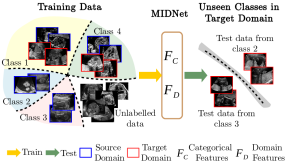

In contrast to the human visual system, DNNs exhibit weak generalizability when confronted with previously unseen entangled image features. This is the problem which we address in this paper. We postulate that DNNs should be able to learn generalizable features to transfer the knowledge from known entangled image features to new entangled image features. As outlined in Fig. 1, we want to improve the performance of DNNs on unseen categories in a target domain where all categories from a source domain and a subset of categories from a target domain are available for training. This task can greatly contribute to diagnostic classification in medical imaging. For example, detecting a certain pathology which rarely occurs in a particular geographic region but might be common in other places.

In this paper, we propose mutual information-based disentangled networks (MIDNet) for representation disentanglement to address the problem outlined in Fig. 1. The proposed approach extracts generalized categorical features by explicitly disentangling categorical features and domain features via mutual information minimization [3]. Note that the categorical features in this paper refer to the features relevant to identities of classes or categories. We introduce the supervision from labeled images for an enhanced disentanglement via a feature clustering module, which estimates the similarity of categorical features from both domains. Image reconstruction is used to guarantee that the separated categorical and domain features are not random noise and are representative for the input images. To further explore an improved categorical classification, we structure a categorical feature space by considering inter-class relationships. On top of the proposed MIDNet model, we incorporate distance metric learning to increase inter-class variance. The proposed method is a non-adversarial method which mitigates the difficulty and instability of adversarial model training. Our method is a semi-supervised learning method, which only requires a small number of labeled samples during training while unlabeled data is integrated using a strategy similar to the MixMatch approach [6].

To solve this task, we propose MIDNet in combination with semi-supervised learning. The architecture of our model is shown in Fig. 4. Two independent encoders are utilized to respectively extract categorical features and domain features from labeled data and unlabeled data . The classifier is responsible for predicting class distributions from for both and while the decoder combines and for the reconstruction of input images. The mixer aims to linearly mix labeled and unlabeled samples so that the model is trained to show linear behavior between samples for further leveraging of unlabeled data. For representation disentanglement, mutual information between and is minimized to encourage to become domain-invariant and maximally informative for categorical classification. Feature clustering contains feature alignment and distance metric learning. Feature alignment aims at keeping the feature consistency between labeled images to promote the independence of . Distance metric learning considers inter-class relationships, which clusters similar samples while separating dissimilar samples to optimize for improving classification performance.

We evaluate the proposed method on two fetal US standard plane classification tasks, where the domain shifts are respectively caused by shadow artifacts (Fig. 2(a)) and different image acquisition devices (Fig. 2(b)). For both tasks, images from source and target domains are unpaired and collected independently. We show the key results in the main paper and detailed implementation, network architectures as well as more results in the supplemental Appendix.

The fetal US dataset consists of 2D fetal US images sampled from 2694 2D US examinations with gestational ages between weeks (iFIND Project 555http://www.ifindproject.com/ ). Eight different US systems of identical make and model (GE Voluson E8) were used for the acquisitions to eliminate as many unknown image acquisition parameters as possible. Six different anatomical standard plane locations have been selected by an experienced sonographer, including Four Chamber View (4CH), Abdominal, Femur, Lips, Left Ventricular Outflow Tract (LVOT) and Right Ventricular Outflow Tract (RVOT). The images have additionally been classified by an expert observer as shadow-containing or shadow-free. In this experiment, the source domain contains shadow-free images (see Fig. 2 (b) SF) while the target domain has shadow-containing images from less favorable imaging conditions (see Fig. 2 (b) SC). Training data consists of all six standard planes from the source domain as well as Abdominal, LVOT and RVOT from the target domain. We aim to separate anatomical features (categorical features) and shadow artifacts features (domain features) to obtain generalized anatomical features for achieving high performance of standard plane classification on (4CH, Femur and Lips from target domain). Here, contains 4CH, Abdominal, Femur, Lips, LVOT and RVOT from the source domain and contains Abdominal, LVOT and RVOT from the target domain. Hyper-parameters to in Eq. 11 are for the proposed MIDNet model and is additionally for MIDNet+.

IV-D Experiments on cross-device fetal US

The previous experiment on fetal US images is supported by data restricted to one US imaging device. Here, we evaluate MIDNet for a standard plane classification task on data from different imaging devices (different device domains). Device A is “GE Voluson E8” which is the same device in Sec. IV-C, which acquired 2D fetal US images. Device B is “Philips EPIQ V7 G” which acquired another images sampled from about 500 2D US examinations with gestational ages between 20-32 weeks (see Fig. 2 (b)). In this experiment, we use four different anatomical standard plane locations with sufficient images in both domains, including Abdominal, Brain, Femur and Lips, which are selected by an 10-year-experienced sonographer. In this experiment, the source domain is set as device A while the target domain is device B. Training data consists of all four standard planes from the source domain as well as Abdominal and Brain from the target domain. We aim to separate anatomical features (categorical features) and imaging device features (domain features) to obtain generalized anatomical features for achieving high performance of standard plane classification on (Femur and Lips). Here, contains Abdominal, Brain, Femur and Lips from the source domain and contains Abdominal and Brain from the target domain. Hyper-parameters to in Eq. 11 are for the proposed MIDNet model and is additionally for MIDNet+.